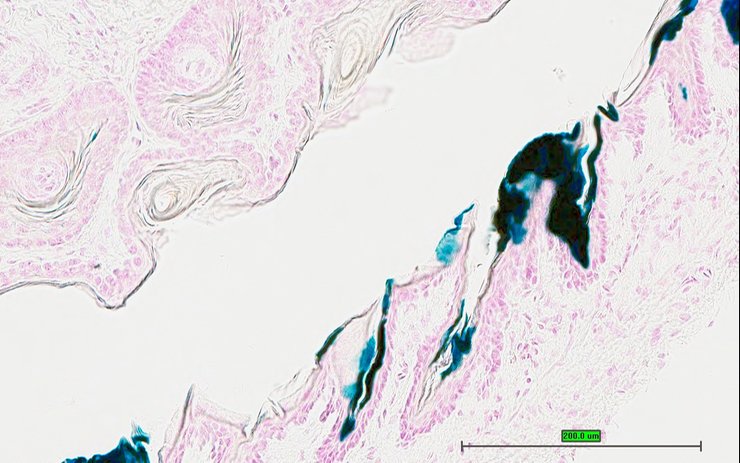

TS28: skin Present UC Davis_1875773

Specimen UC Davis_1875774: postnatal adult; Calcbtm1.1(KOMP)Vlcg/Calcb+ (more )

Structure Level Pattern Image Note

TS28: skin Present UC Davis_1875774

TS28: skin Present UC Davis_1875788

Specimen UC Davis_1875789: postnatal adult; Calcbtm1.1(KOMP)Vlcg/Calcb+ (more )

TS28: skin Present UC Davis_1875789